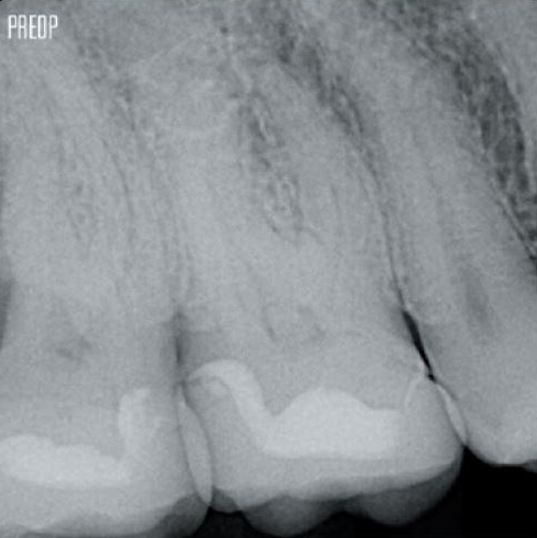

Davantage de dentine préservée. Mise en forme, irrigation et obturation appropriées.

Photos avec l’aimable autorisation du Dr Ahmed Salman